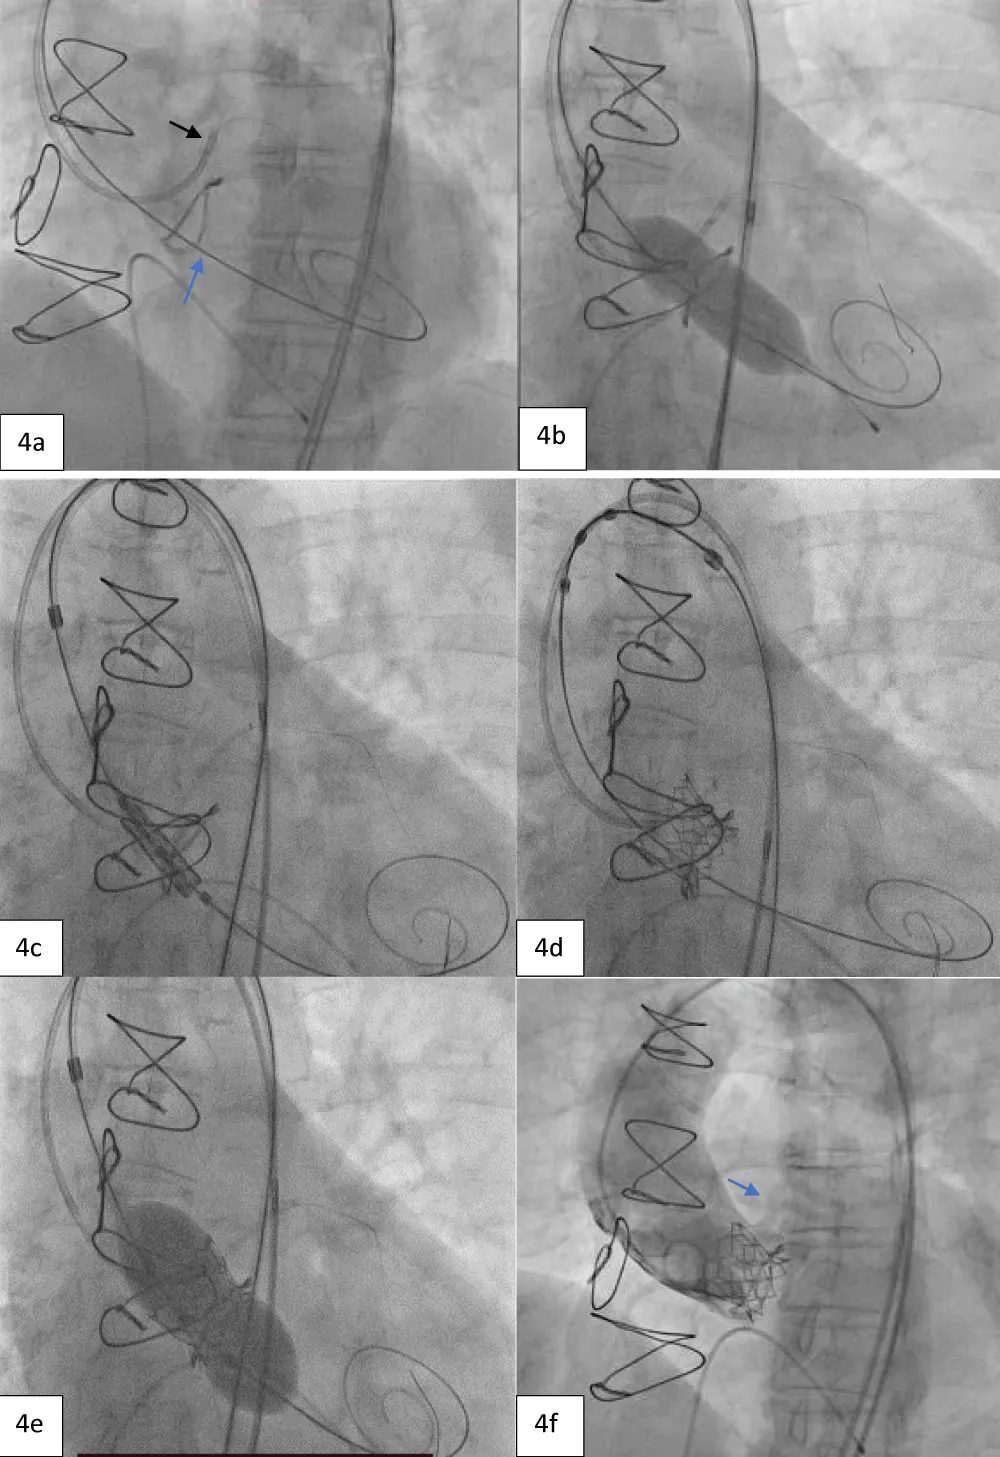

The TAVI was started by placing the patient under conscious sedation. An AL-1 catheter and a straight-tip Terumo wire (GLIDEWIRE® Standard, Terumo Corporation, Tokyo, Japan) were utilized to cross the valve. Subsequently, the AL-1 catheter was exchanged with a pigtail catheter, and a Safari extra support stiff guidewire (Boston Scientific Corporation, Marlborough, Massachusetts, USA) was placed at the LV apex for observing the periprocedural hemodynamics (i.e., the mean and peak pressure gradients). Then, a pacing lead wire was inserted into the right ventricle through the left femoral vein and a guiding catheter was inserted into the left CFA to protect the LCO (Figure 4a). The larger 14-Fr Python Introducer Sheath (Meril Life Sciences Pvt. Ltd., India) was advanced into the right CFA for THV delivery.

Next, we performed LMCA cannulation using a 6-Fr extra support backup guiding catheter (Medtronic, Minneapolis, USA) followed by placing a 180-cm long, 0.014” Runthrough® straight-tip coronary guidewire (Terumo Medical Corporation, Tokyo, Japan) through the LAD and placing a guide extension catheter in the LMCA (Guidezilla II; Boston Scientific Corporation, Marlborough, Massachusetts, USA) (Figure 4a). This ensured the adequate coronary protection of the LMCA. We proceeded with pre-dilatation for the deployment of the Myval THV using a 20 × 40 mm Mammoth™ balloon (Figure 4b) and deploying the 21.5 mm Myval THV under rapid pacing (Figure 4c,4d). After valve deployment, the patency of LMCA was evaluated by running an aortogram. One post-dilatation was performed using the same balloon by the addition of an extra 2 cm3 inflation volume (Figure 4e) followed by an evaluation of post-valve deployment patency of LMCA on the aortogram (Figure 4F). Upon confirming the final patency of the LMCA, the guide extension catheter from the LMCA and the guidewire from the LAD were gradually retracted. On the postprocedural echocardiogram, the residual peak-to-peak gradient across the left ventricle (LV) and aorta was 9 mmHg (Figure 5), and the mean and peak gradients were 8 mmHg and 8 mmHg. The procedure was completed by wound sealing at the right femoral site with one Proglide® and one Angio-seal® suture (St Jude Medical, St Paul, Minnesota, USA).

Download Image

Figure 4: Showing protection of left main artery with guide extension catheter and guidewire (black arrow) and Safari stiff wire across the previous prosthetic valve (blue arrow). b. Pre-dilatation with 20x40 mm Mammoth balloon. c. Positioning of 21.5 mm Myval across the previous bioprosthetic valve. d. Deployment of the BE Myval THV with coronary protection in situ. e. Post dilatation performed using the same Mammoth over-the-wire balloon. f. Final aortic root angiogram showing patent LMCA (blue arrow).